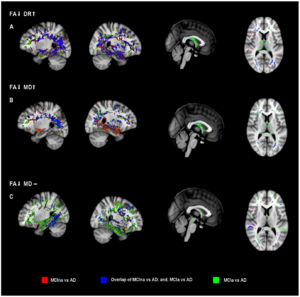

Potential of Diffusion Tensor Imaging and Relaxometry for the Detection of Specific Pathological Alterations in Parkinson's Disease (PD)

Publication: PLoS One. 2015 Dec 29;10(12):e0145493. PMID: 26713760 | PDF Authors: Esterhammer R, Seppi K, Reiter E, Pinter B, Mueller C, Kremser C, Zitzelsberger T, Nocker M, Scherfler C, Poewe W, Schocke M. Institution: Department of Radiology, University Hospital, Innsbruck Medical University, Innsbruck, Austria. Background/Purpose: The purpose of the present study was to evaluate the potential of multimodal MR imaging including mean diffusivity (MD), fractional anisotropy (FA), relaxation rates R2 and R2* to detect disease specific alterations in Parkinson's Disease (PD). We enrolled 82 PD patients (PD-all) with varying disease durations (≤5 years: PD≤5, n = 43; >5 years: PD>5, n = 39) and 38 matched healthy controls (HC), receiving diffusion tensor imaging as well as R2 and R2* relaxometry calculated from multi-echo T2*-weighted and dual-echo TSE imaging, respectively. ROIs were drawn to delineate caudate nucleus (CN), putamen (PU), globus pallidus (GP) and substantia nigra (SN) on the co-registered maps. The SN was divided in 3 descending levels (SL 1-3). The most significant parameters were used for a flexible discrimination analysis (FDA) in a training collective consisting of 25 randomized subjects from each group in order to predict the classification of remaining subjects. PD-all showed significant increases in MD, R2 and R2* within SN and its subregions as well as in MD and R2* within different basal ganglia regions. Compared to the HC group, the PD≤5 and the PD>5 group showed significant MD increases within the SN and its lower two subregions, while the PD≤5 group exhibited significant increases in R2 and R2* within SN and its subregions, and tended to elevation within the basal ganglia. The PD>5 group had significantly increased MD in PU and GP, whereas the PD≤5 group presented normal MD within the basal ganglia. FDA achieved right classification in 84% of study participants. Micro-structural damage affects primarily the SN of PD patients and in later disease stages the basal ganglia. Iron contents of PU, GP and SN are increased at early disease stages of PD. Funding:

The regions-of-interest (ROIs) were manually drawn by an experienced radiologist by using the b 1000 images, averaged for all measured directions, the FA maps and the proton-density weighted images. For that purpose, the maps of ADC, FA, R2 and R2* as well as the proton-density weighted images were first co-registered. The ROIs were segmented by syncing the b 1000 images, averaged for all measured directions, the FA maps and the proton-density weighted images in ImageJ. The ROIs were stored in the ROI manager and transferred to the co-registered maps. The segmented brain regions were highlighted in different colors: CN—black; PU—red; GP—green; TH—white; SN—blue; CC—cyan. The diffusion-weighted images, the R2 and R2*-weighted maps were transferred to the 3D Slicer software in order to co-register the R2 and the R2* maps as well as the MD and the FA maps |